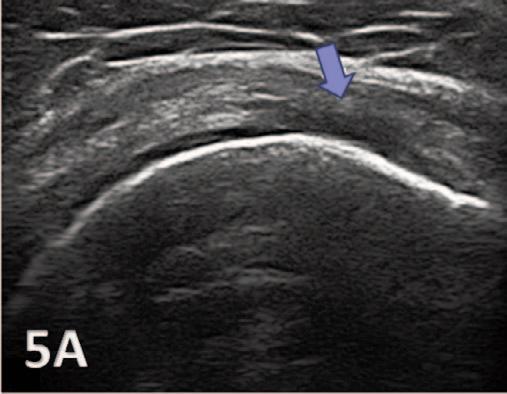

935 Utilizing Diagnostic Musculoskeletal Ultrasound for Assessment of the Infraspinatus Muscle and Tendon: Implications for Rehabilitation Professionals. Manske RC, Voight M, Wolfe C, Page P.